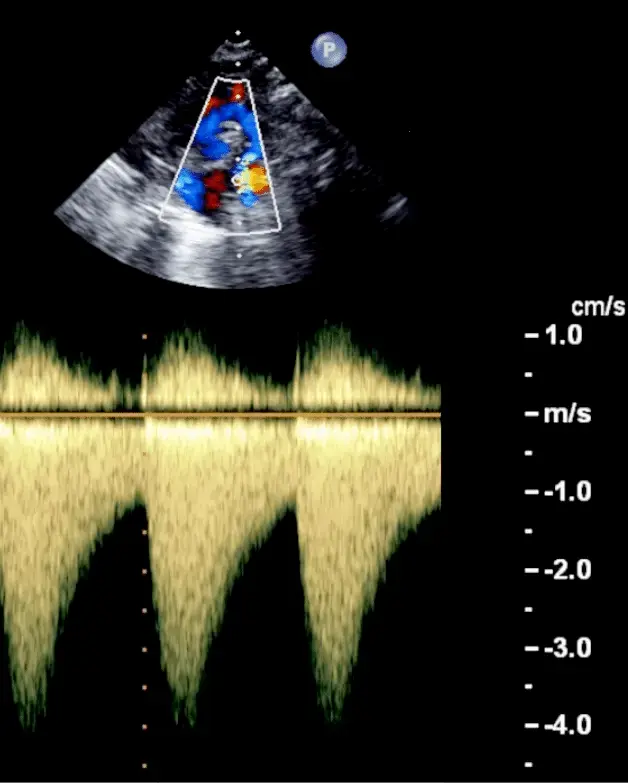

Echo for Valvular AS

- Cannot tell severity of stenosis with 2D-echo alone. You will need Doppler to help determine severity of AS.

- ==Valvular AS will be considered severe if mean gradient > 40 mmHg or peak velocity > 4 m/s (regardless of AVA)==

- ⚠️ With mixed aortic valve disease, significant AR can increase peak aortic valve velocity and mean aortic valve gradients because of high flow.

- Aortic velocity is measured using continuous-wave doppler ultrasound with examination from multiple acoustic windows

- Mean gradient is calculated by averaging instantaneous gradients over the systolic ejection period using the modified Bernoulli equation,

Underestimation due to improper Doppler alignment across the Aortic Valve

If not parallel to the AS jet, you will not get the highest mean AV gradient or peak velocity across the AV → underestimate severity of AS. Importantly, you cannot overestimate the gradient (Exceptions: significant anemia or Subaortic Stenosis).